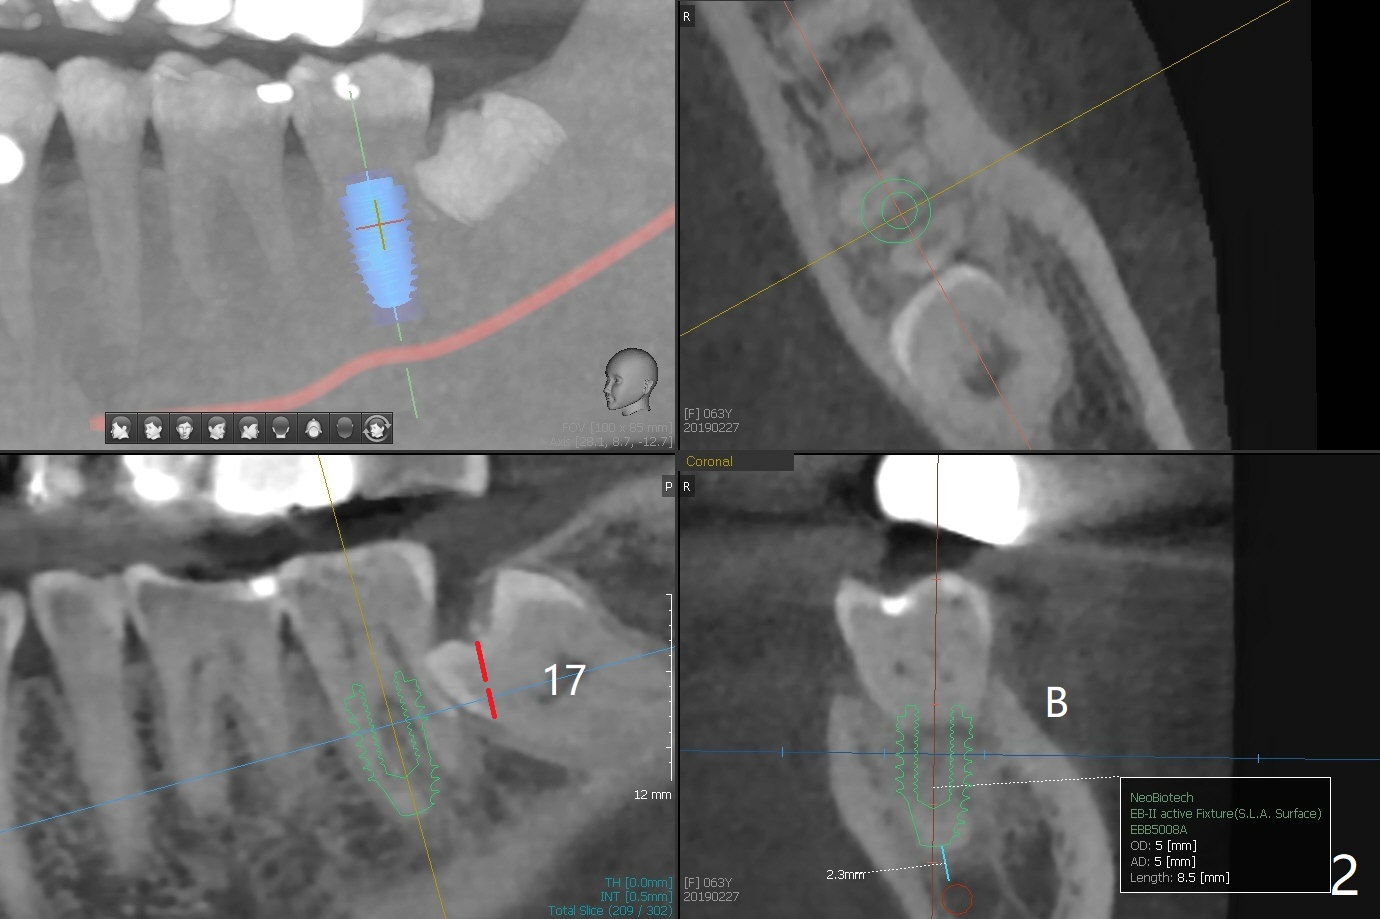

A 63-year-old woman wants to extract the tooth #18 with crack before termination of dental insurance (Fig.1). It is also possible to place an immediate implant in the septum (Fig.2). Socket shield is not needed because of the wide bone. If the implant is too close to the tooth #17, section the mesial portion of the latter (red dashed line), since removing the impacted tooth may risk injury to the Inferior Alveolar Canal (Fig.3,4). Draw one tube of blood for sticky bone.